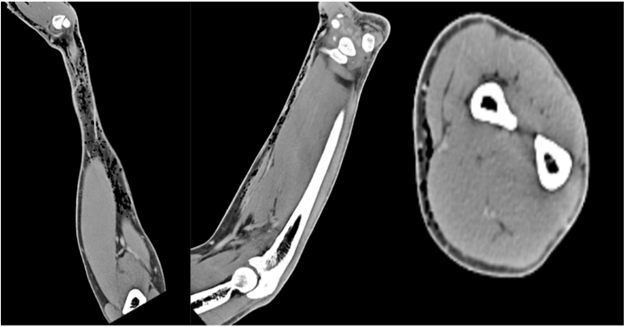

A 64-year-old right-hand-dominant male with no medical history presented with a swollen, painful right hand 10 h after a pen knife injury to the first web space. He irrigated the wound with hydrogen peroxide, but developed mild local numbness, tingling, and swelling 6 h later. He denied fever or chills. Examination revealed diffuse subcutaneous crepitus on the dorsum of the hand and forearm with intact distal sensation. Tetanus vaccination was updated. Vital signs were stable. Radiographs showed widespread SE, prompting an orthopedic consultation. The patient was admitted for observation to rule out NF. A contrast-enhanced computed tomography (CT) confirmed SE extending to the deltoid without abscess or cortical destruction (Fig. 2, 3, 4). Empiric IV antibiotics (Vancomycin, Zosyn, and Clindamycin) were initiated.

Figure 4: Computed tomography of right arm with contrast reveals no focal cortical destruction or osseous abnormality. There was mild soft tissue emphysema tracking and interspersed in the mid deltoid muscle with no drainable abscess.